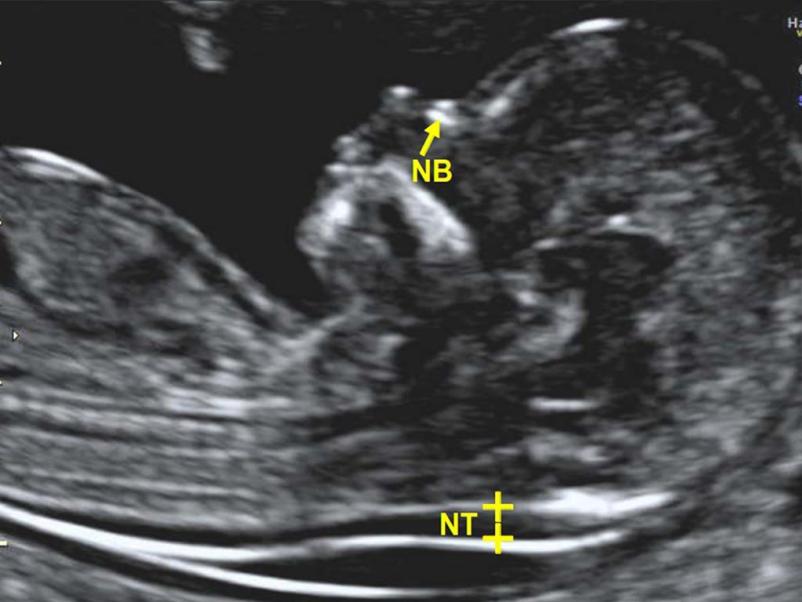

Znani smo po celoviti, profesionalni specialistični obravnavi naših pacientk, katerim so na voljo ginekološke, porodniške in druge ambulantne storitve, vključno z ultrazvokom in merjenjem nuhalne svetline, ki jih opravljamo diskretno in tako, da so za pacientke kar najmanj neprijetne.